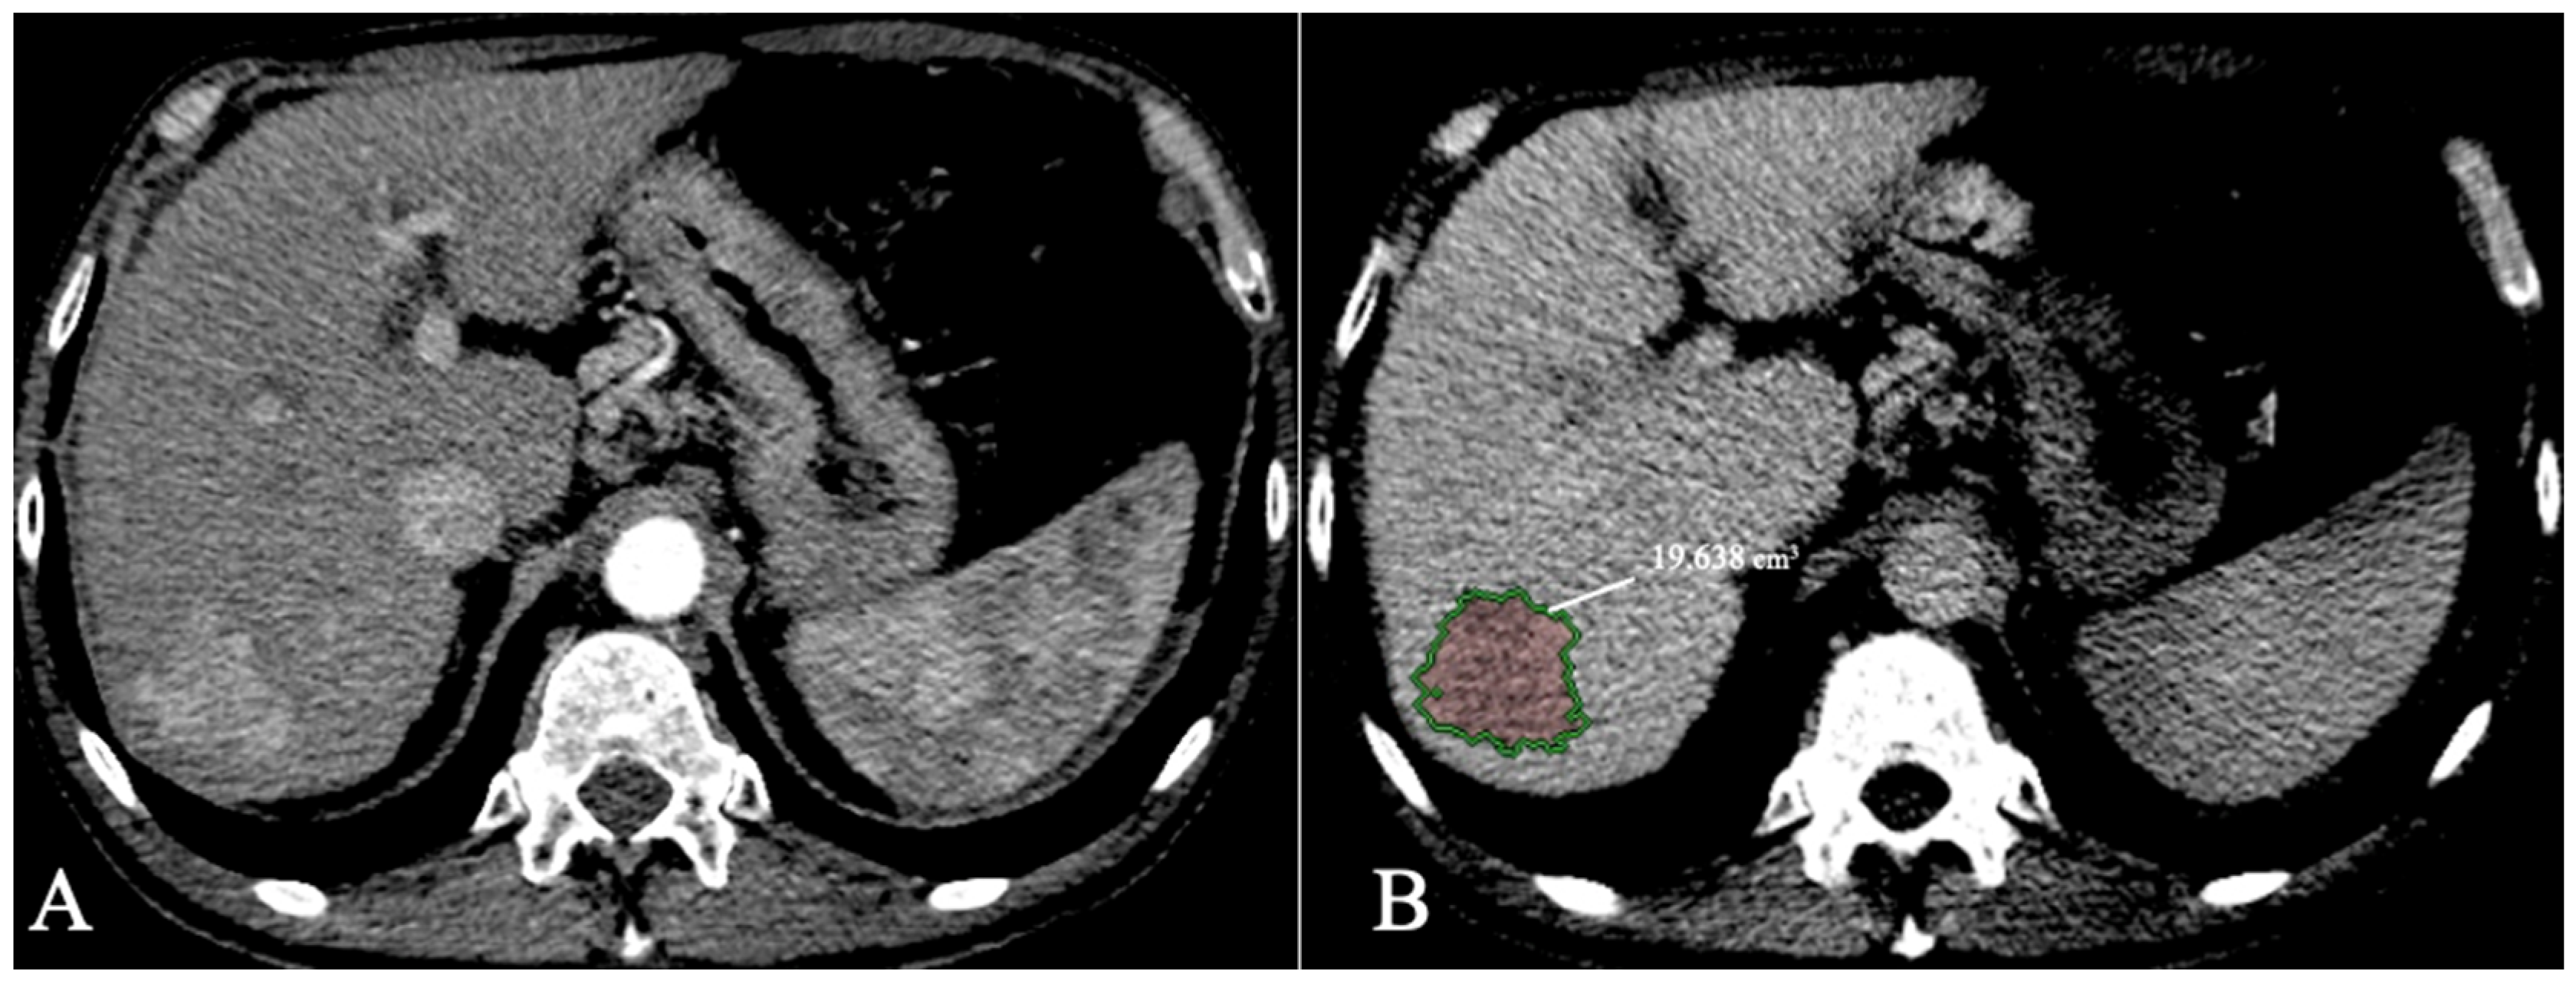

- Bousabarah, K.; Letzen, B.; Tefera, J.; Savic, L.; Schobert, I.; Schlachter, T.; Staib, L.H.; Kocher, M.; Chapiro, J.; Lin, M. Automated detection and delineation of hepatocellular carcinoma on multiphasic contrast-enhanced MRI using deep learning. Abdom. Radiol. 2021, 46, 216–225. [Google Scholar] [CrossRef] [PubMed]